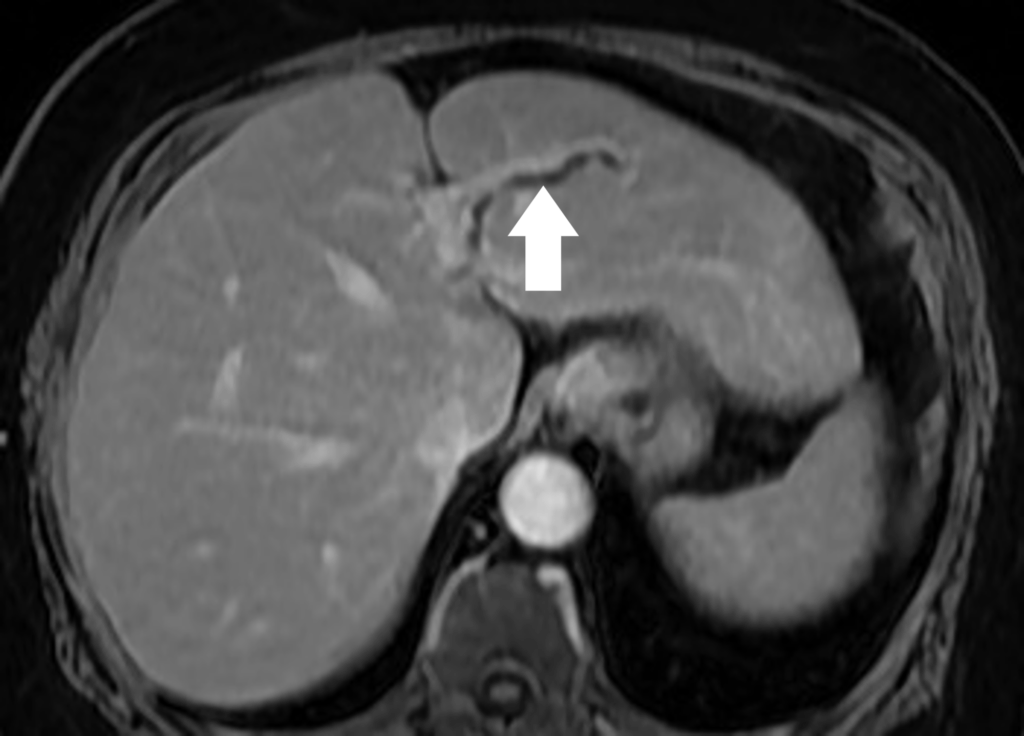

59歲陳女士長期承受間歇性腹痛,九月間於外院住院治療仍無改善,出院後轉至臺中市立老人復健綜合醫院。於肝膽腸胃科由內科部部長賴學洲醫師安排腹部超音波及核磁共振檢查,確診為左側肝內結石合併慢性肝內膽管炎及膽囊細沙併慢性膽囊炎,後經一般外科主任曹連誠醫師評估,安排 3D 立體內視鏡左肝切除加膽囊切除手術。患者術後恢復良好,第二天即可下床行走,自理生活,成功擺脫惱人的腹痛與長年不適。

肝臟及膽道手術過去大多以開腹方式進行,術後疼痛及恢復期長。此次採用的3D 立體內視鏡技術可清晰呈現肝臟內細微結構,3D立體視角搭配螢光血流影像,即時辨識血管與膽管位置,提高手術安全性與精準度。15 公分大的肝臟組織,僅透過約 5 公分傷口取出,可大幅降低術後疼痛與感染風險,縮短住院及復原時間,保留最多肝臟功能,同時避免肝內膽管癌長期風險。